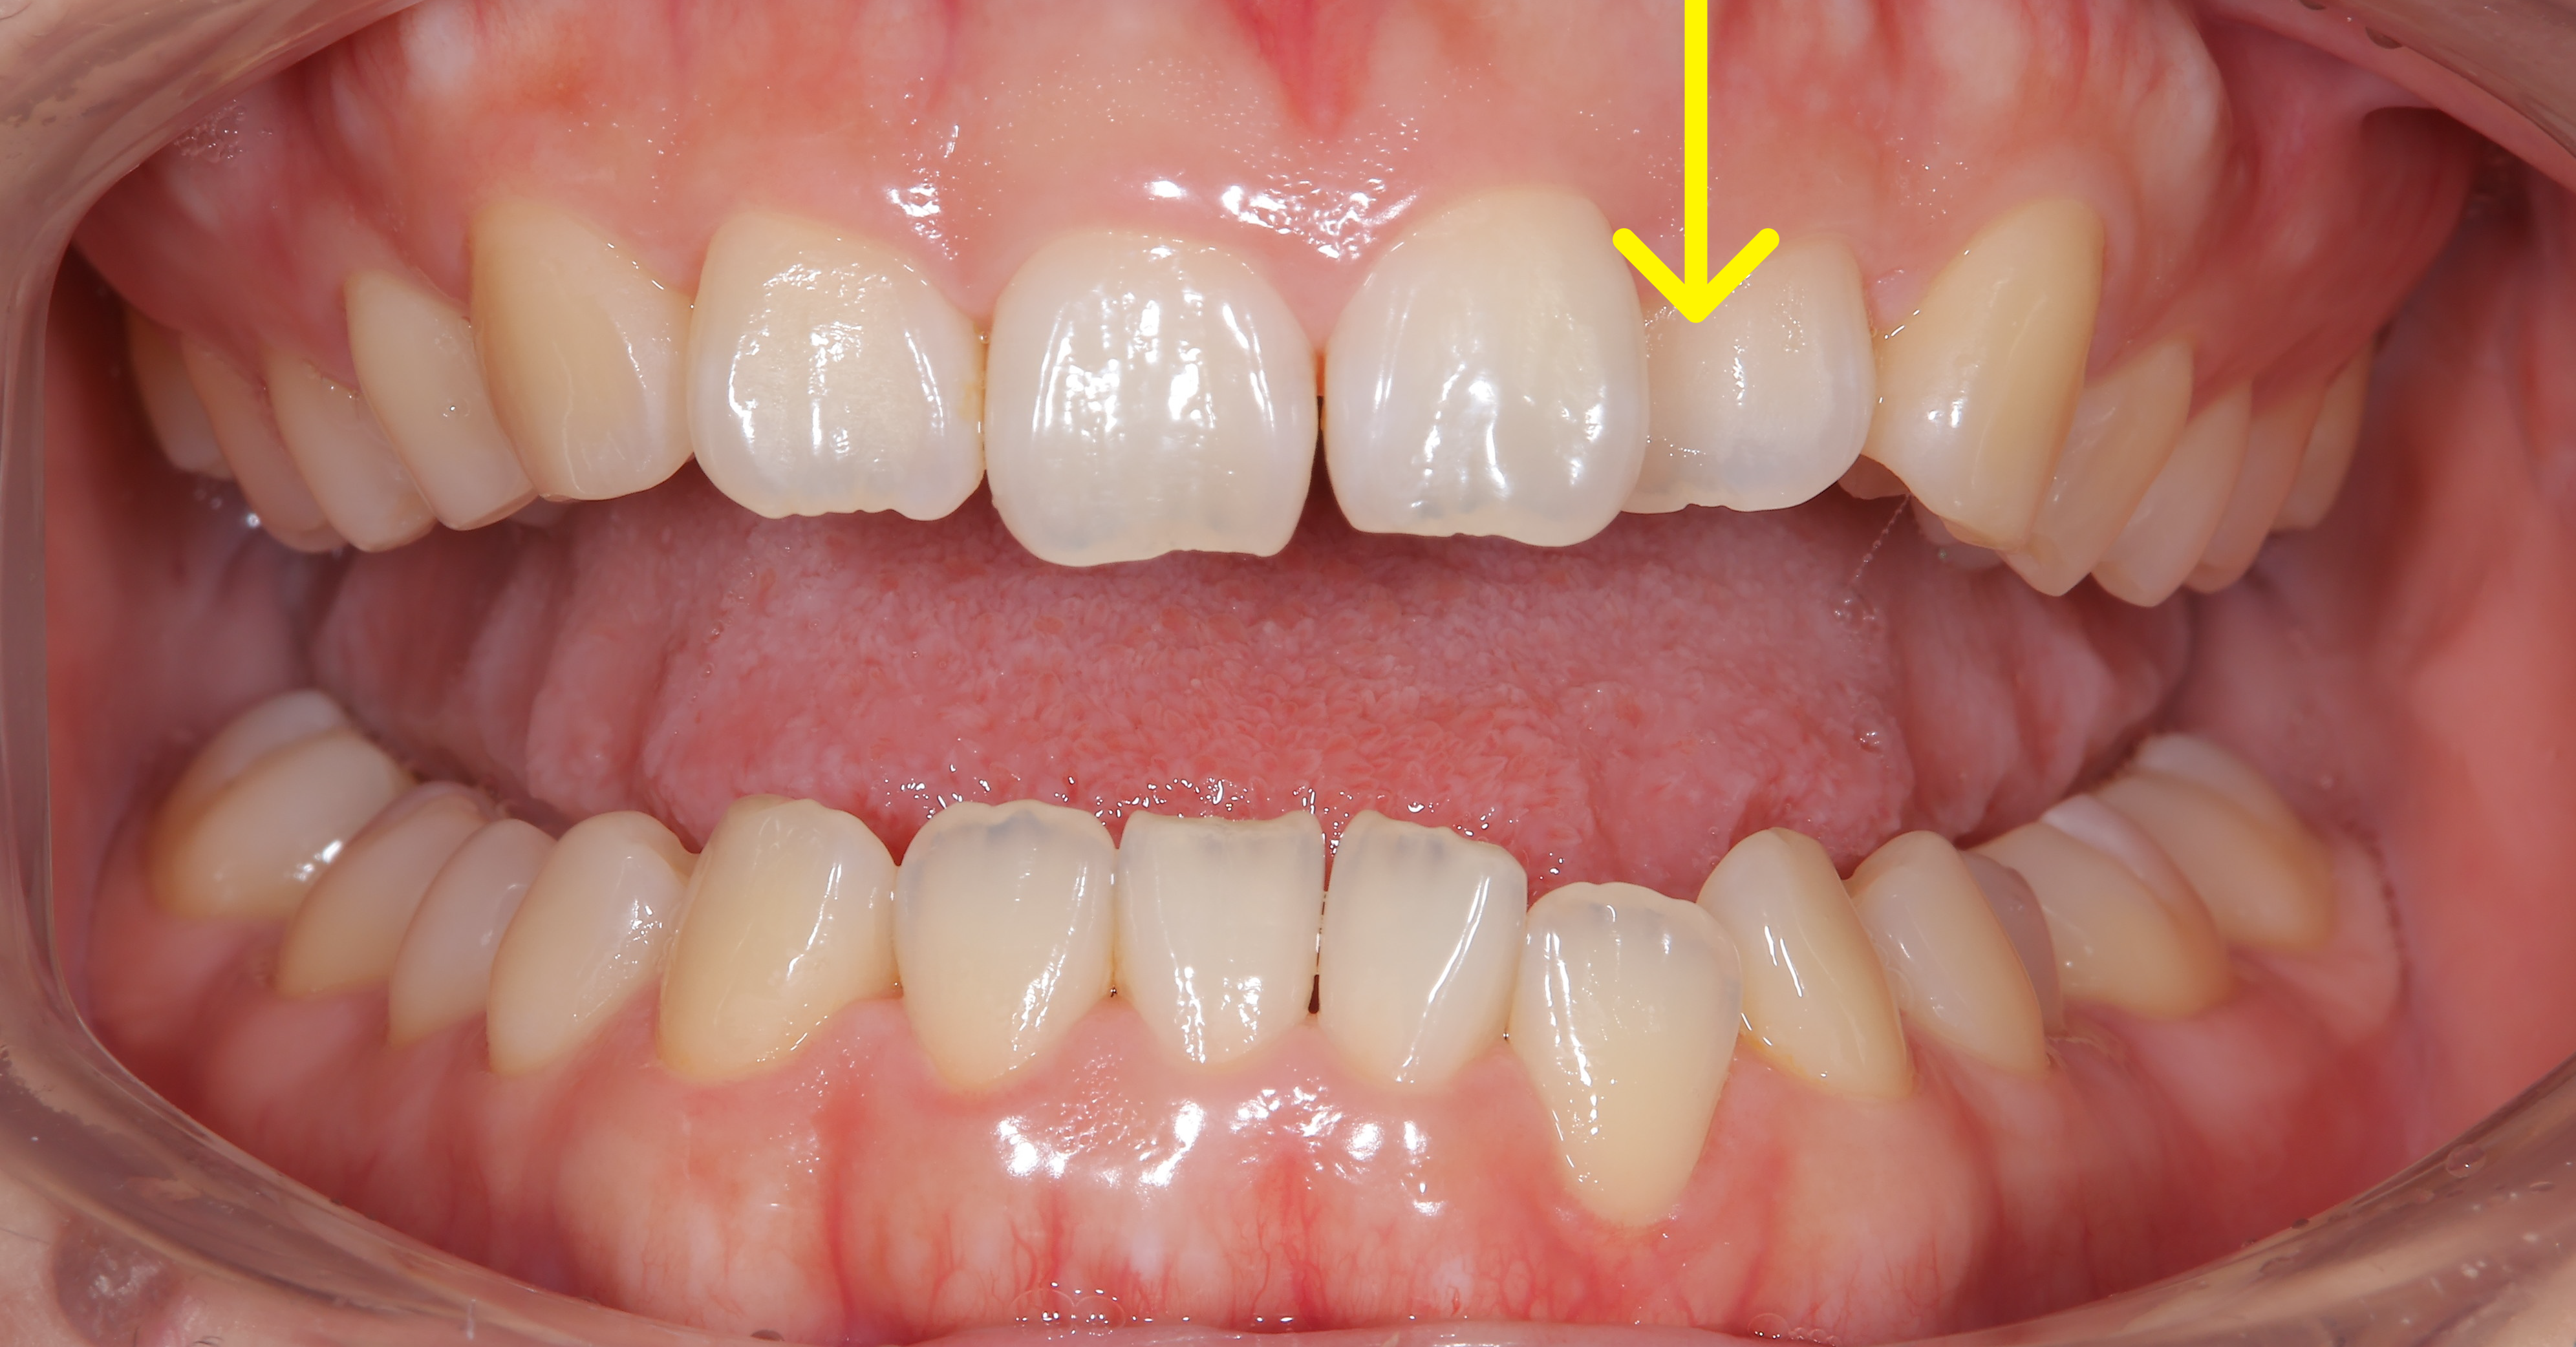

治療概要:矢印の歯は反対咬合(上の歯より下の歯の方が前に出ている)になっています。また、この方も過蓋咬合で下の前歯がほとんど見えません。

奥歯の噛み合わせはほとんど問題なく、マウスピース矯正を提案し矯正スタートしました。マウスピース矯正は食事中は外せたり、歯磨きもしっかりできるので良い治療法ですが、2番目の歯などあまり凹凸の少ない歯は動きが悪いことがあります。

ほぼ他の歯が並んだ状態でも、やはりこの矢印の歯だけ動きが悪かったのと、左下の捻れた歯がなかなか治らなかったので、ワイヤーを部分的に使用させてもらいました。

下の写真が術前術後の比較です。下の前歯が見えるようになりました。上の前歯の傾きが変わるだけで口元の印象も変化します。